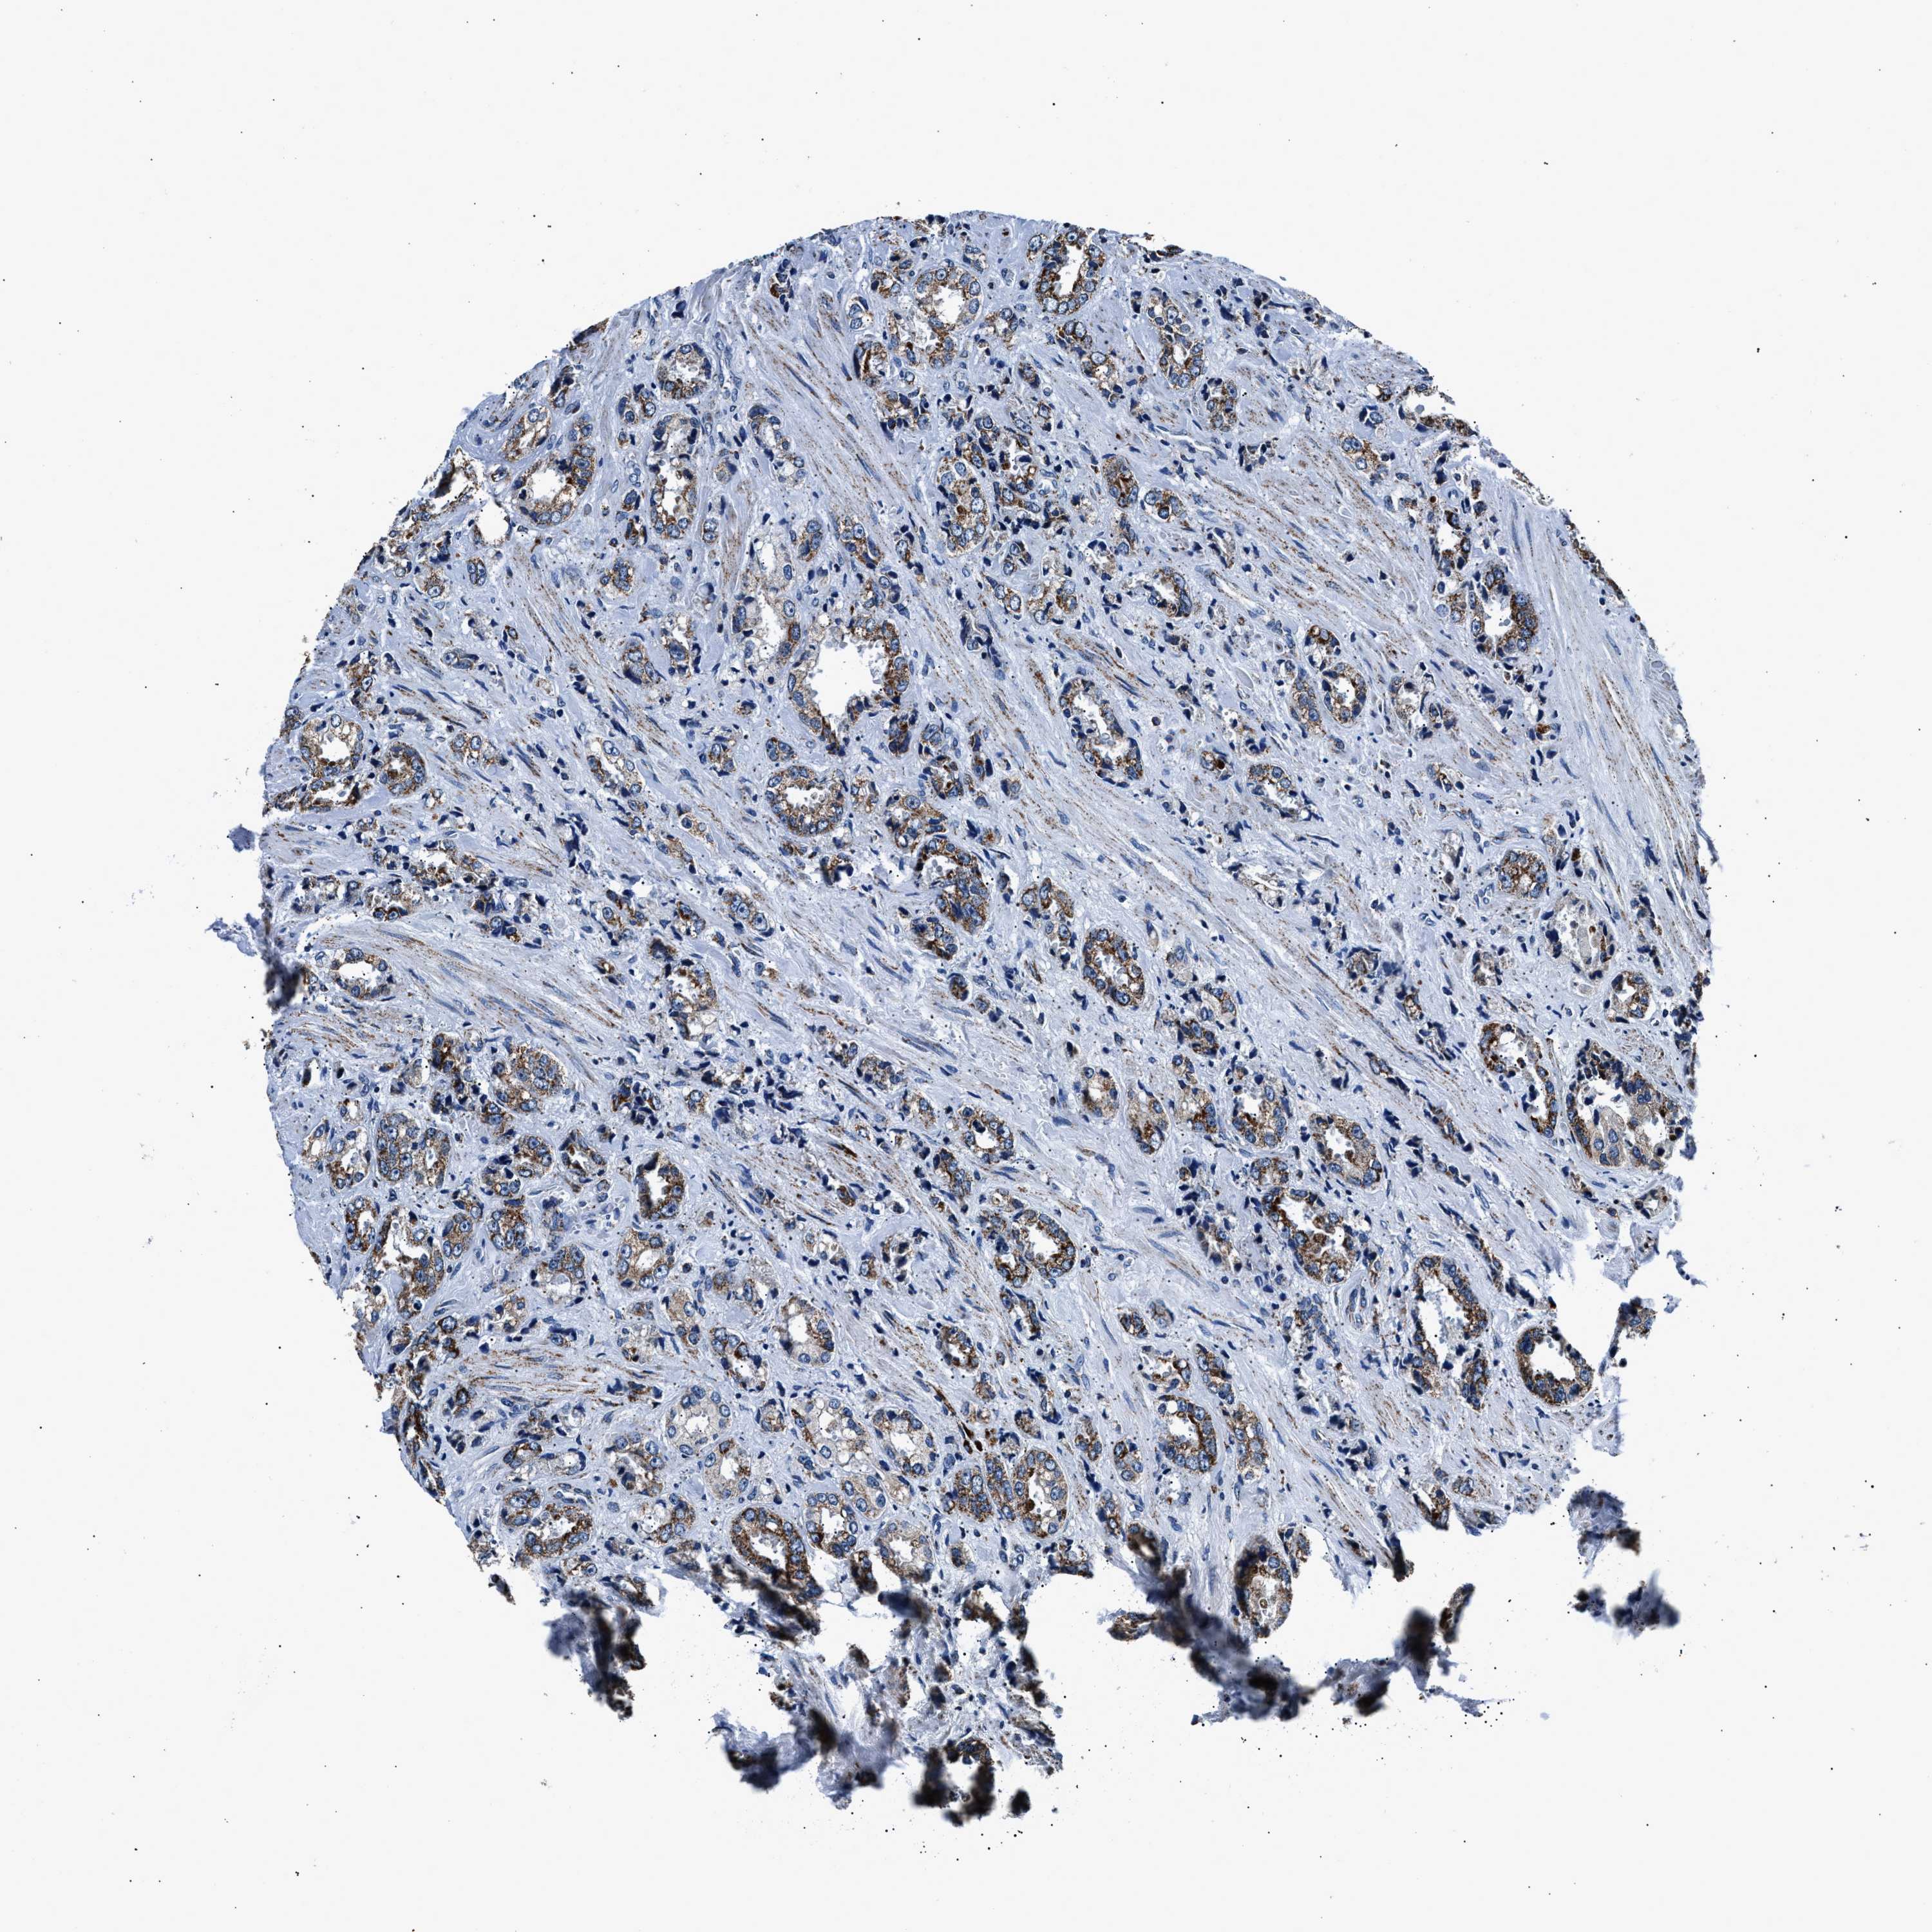

PROSTATE CANCER - Protein expressioni

A mouse-over function shows sample information and annotation data. Click on an image to view it in a full screen mode. Samples can be filtered based on level of antibody staining by selecting one or several of the following categories: high, medium, low and not detected. The assay and annotation is described here.

Note that samples used for immunohistochemistry by the Human Protein Atlas do not correspond to samples in the TCGA dataset.

Antibody stainingi

Antibody staining in the annotated cell types in the current human tissue is reported as not detected, low, medium, or high, based on conventional immunohistochemistry profiling in selected tissues. This score is based on the combination of the staining intensity and fraction of stained cells.

Each image is clickable and will lead to virtual microscopy that enables deeper exploration of all samples and also displays staining intensity scores, fraction scores and subcellular localization as well as patient and tissue information for each sample.

Antibody HPA019522

Antibody HPA021002

Staining

High

Medium

Low

Not detected

Intensity

Strong

Moderate

Weak

Negative

Quantity

>75%

75%-25%

<25%

None

Location

Nuclear

Cytoplasmic/membranous

Cytoplasmic/membranous,nuclear

Adenocarcinoma, High grade

Adenocarcinoma, Low grade